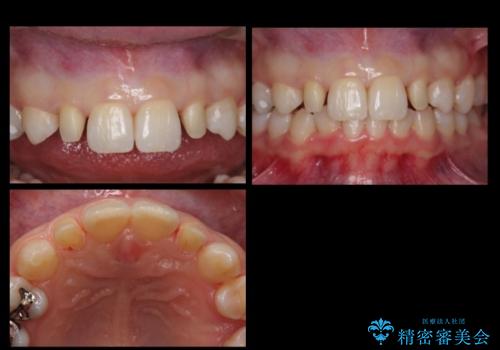

抜歯したスペースを使い、歯並びを整え、さらにその隙間を利用して細い歯を大きく整えてセラミックで被せるという総合的な治療を行いました。

マウスピース矯正→上顎両側2番のセラミック、左下67の虫歯治療 の順で行いました。

- 137万円 内訳:矯正治療95万円 セラミック治療42万円 (前歯2本28万円(ジルコニアクラウン・スペシャル) 左下奥歯2本15万円(emaxインレー、ヴェレッツァクラウン))ホワイトニング(エクセレント)3万円費用は治療当時の料金となります

矯正治療→ホワイトニング→セラミック の順で行なっています。

ホワイトニングで綺麗に白くした歯に合わせて、被せています。